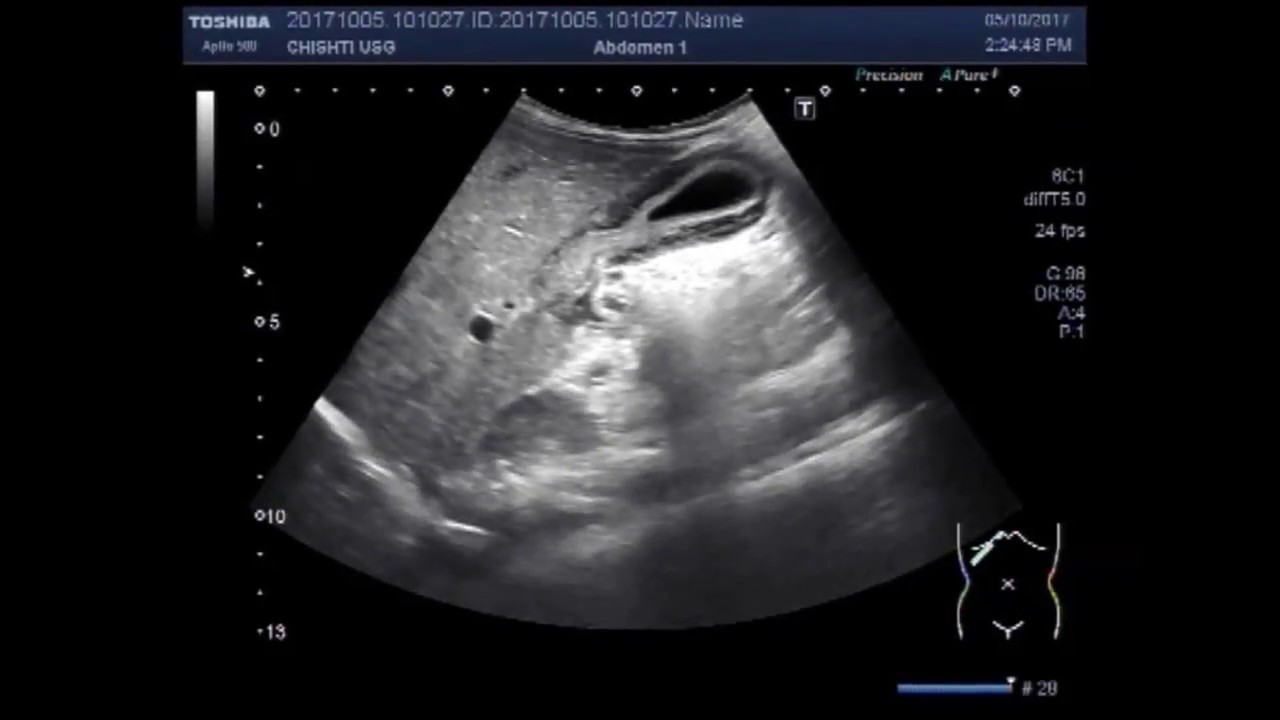

ACUTE & CHRONIC VIRAL HEPATITIS Ultrasound, echography ACUTE & CHRONIC

Acute Hepatitis Ultrasound Lecture Imaging Study YouTube Hcv Ultrasound If acute hepatitis c virus (hcv) infection is suspected (hepatitis c antibody positive with clinical features of acute hepatitis. Almost all adult patients with cirrhosis and some patients with chronic hepatitis b virus (hbv) are at sufficiently high risk for. Ultrasound can detect large hepatocellular carcinomas (hccs) with high sensitivity and specificity. However, detection of lesions below 2cm by ultrasound. Hcv Ultrasound.

Ultrasound Liver Disease Acute Viral Hepatitis YouTube Hcv Ultrasound If acute hepatitis c virus (hcv) infection is suspected (hepatitis c antibody positive with clinical features of acute hepatitis. Hcv infection is diagnosed with an antibody test (which indicates if a person has ever been infected with hcv) and hcv ribonucleic acid. However, detection of lesions below 2cm by ultrasound is. Ultrasound can detect large hepatocellular carcinomas (hccs) with high. Hcv Ultrasound.